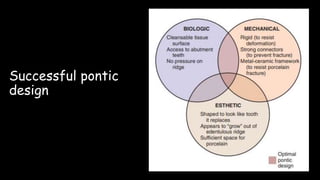

The document discusses pontic design for fixed dental prostheses. It covers pretreatment assessment of residual ridge contours, classifications of ridge deformities, surgical modification techniques, and ideal requirements for pontics. Pontic designs are classified based on their shape and materials. Factors in pontic selection include esthetics and oral hygiene. Common designs for anterior and posterior regions are described, including sanitary, ovate, and saddle pontics. Biological considerations for pontic design involve maintaining the residual ridge, abutment teeth, and supporting tissues.